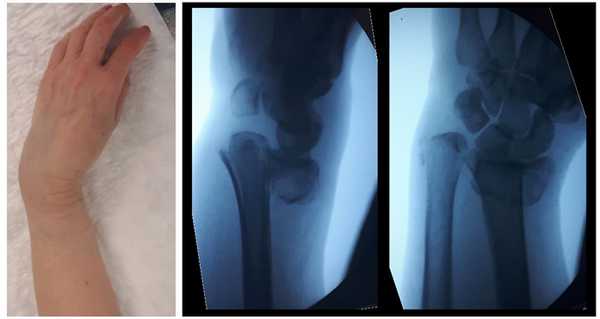

Внешний вид конечности после снятия гипсовой повязки. Рентгенограммы выполненные при помощи ЭОП на операционном столе выявили полное смещение всего дистального метафиза лучевой кости к тылу на целый поперечник.

Внешний вид конечности после операции, угловая деформация устранена. Сегмент конечности стабилен, движения в локтевом и лучезапястном суставах не ограничены, ротация предплечья ограничена из-за наличия позиционного винта, который будет удаляться через 6 недель.

Реннтгенограммы после операции.